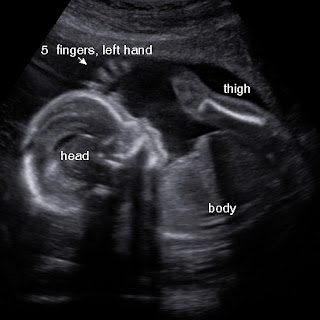

Went in for an elective Ultrasound this morning at 17w3d. We are extremely happy to share It's A Boy!! It was 100% obvious too, he was showing off. When my husband seen it on the screen he gave a little fist pump because he was hoping for a boy. Not long after the tech caught a picture of the baby giving a fist pump! It was so cute, already copying daddy, lol. Just had to share.